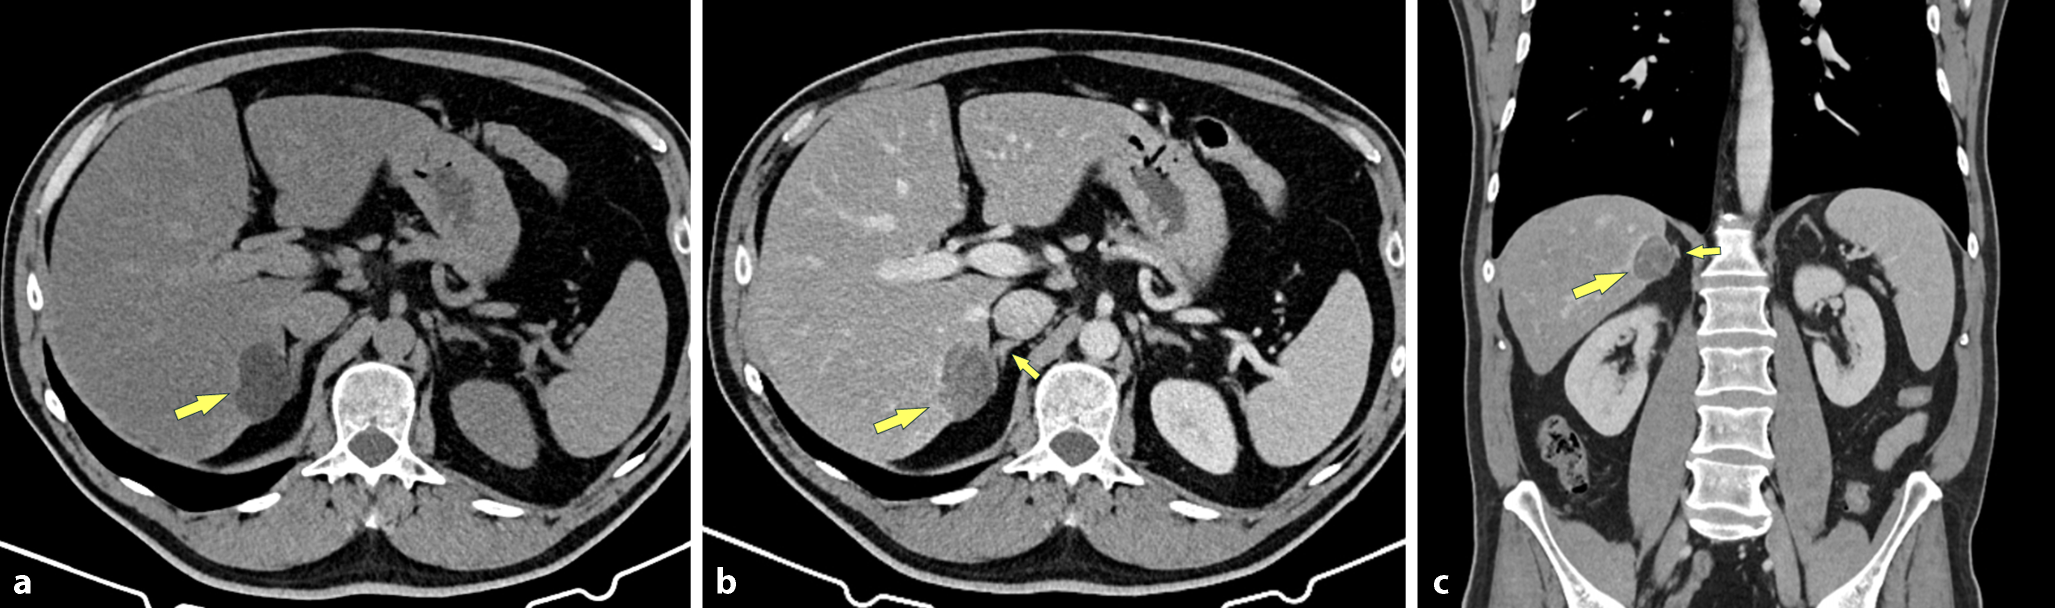

Bei einem 50-jährigen Patienten wurde auswärts in einer Sonographie eine unklare Raumforderung im rechten Leberlappen festgestellt. Der Patient wies keine Vorerkrankungen auf, keine chronische Lebererkrankung, die Leberfunktionsparameter waren im Normbereich. Es wurde daraufhin eine Kontrastmittel-verstärkte Multidetektor-CT (MDCT) durchgeführt, welche eine ausgeprägte diffuse Steatose der Leber zeigte, mit einer 3,9 cm großen subkapsulären Raumforderung im rechten Leberlappen (S 6/7). Diese Läsion war eindeutig Fett-hältig (Dichte nativ, −8 HU) und zeigte nach Kontrastmittel (KM) ein geringes Enhancement (Abb. 1). Zur weiteren Abklärung wurde der Patient an unsere Abteilung verwiesen, wo eine Magnetresonanztomographie (MRT) mit extrazellulärem Gadolinium-hältigem KM durchgeführt wurde. Auch in der MRT zeigte sich eine ausgeprägte Verfettung des Tumors und eine Kontrastmittelaufnahme (Abb. 2). Abgesehen von der diffusen Steatose der Leber fand sich kein Hinweis auf eine Lebererkrankung.

Abb. 1

Die MDCT zeigt a In der Nativserie eine 3,9 cm große, Fett-hältige Raumforderung im Lebersegment 7 subkapsulär (Pfeil) und eine diffuse Dichteminderung der Leber als Ausdruck einer Steatose. Die KM-verstärkte MDCT b axial und c oronal zeigt eine Kontrastmittelaufnahme des Tumors (Pfeil) und auch die Nahebeziehung zur rechten Nebenniere (kleiner Pfeil). Der Ursprungsort der Raumforderung ist aber eindeutig in der Leber